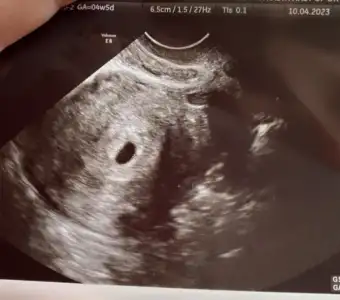

4 gün önce 4+6, iken alttan muayeneyle gordum canımBende hele bugün hiç bişi yok keseyi ne zaman gördün?

Adete göre saymıyor mu? Ben şuan 5+1 oluyorum pazartesi 4+5 de gördüm. Senin kese fotisi var mı? Atsana4 gün önce 4+6, iken alttan muayeneyle gordum canım

Yok benim hiç adet tarihimi sormadi bile keseye baktı 4 buçuk haftalik dediAdete göre saymıyor mu? Ben şuan 5+1 oluyorum pazartesi 4+5 de gördüm. Senin kese fotisi var mı? Atsana

13 Mart adet günümün ilk günüydü. 27 martta aşılama oldum 9 Nisan da test pozitif gördüm pazartesi 10 Nisan da kan verdim 627.2 çıktı canım çarşamba verdim 1447.67 çıktı doktorum cuma keseyi görürüz dedi yarın gideceğimBeta ve gününüz kaç acaba?ben de Cumartesi başka bir doktordan randevu aldım kese için kendi doktorum daha bakmak istemedi. Benim beta 2 katı olarak giderse 4000 küsürlerde olacak günüm de 4+6

Benimki henüz bu aşamada yaaYok benim hiç adet tarihimi sormadi bile keseye baktı 4 buçuk haftalik dedi